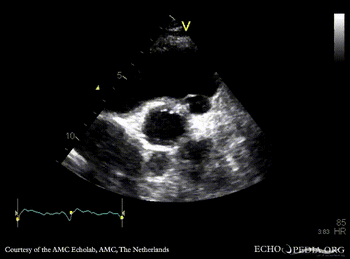

Abscess of aortic valve prosthesis

PSAX: mechanical aortic valve prosthesis, abscess cavity PSAX with Color Doppler